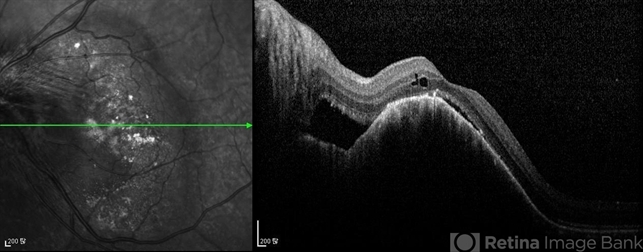

- optical coherence tomography (OCT), choroidal metastasis

- Imaging device

- Optical coherence tomography system

- Optical coherent tomography of an 64-year-old man with bilateral choroidal metastasis of non-small-cell lung cancer.